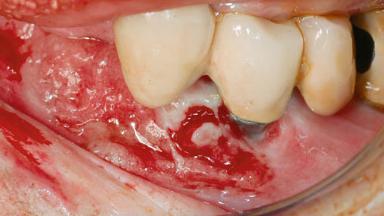

Oral implants are highly successful and offer long-term benefits, especially in the rehabilitation of edentulous patients or patients with oral defects following ablative tumor surgery (Albrektsson and coworkers 1986), and also after radiation therapy (Schiegnitz and coworkers 2014). With the number of implants placed globally going into the millions, implant dentists have observed some rare adverse events. Although carcinogenesis around implants is an exceedingly rare phenomenon, we recently reported about 15 patients treated for carcinomas adjacent to implants at our clinical department over a period of fifteen years (Moergel and coworkers 2014). The following case represents a patient of this cohort; it discusses possible risk factors and makes suggestions for a recall schedule. A 70-year-old woman was referred to our outpatient department for evaluation of a rapidly growing macroscopic alteration of the mucosa in the left mandible.